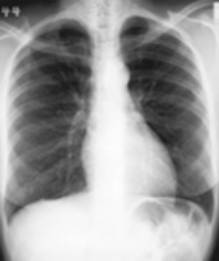

RX thorax

Thorax

Dit is het meest uitgevoerde onderzoek op de dienst radiologie. Een thoraxfoto kan om veel redenen worden aangevraagd.

Als routine onderzoek bij een screening vb. arbeidsgeneeskunde, pre- en post operatief

Bij vermoeden van een longletsel

Bij kortademigheid

Als opvolging van het effect van een behandeling

Bij een trauma van de borstkas

Er zijn in princiepe twee manieren om een thorax opname te maken:

De staande opname waar meestal een face en een profiel opname wordt genomen

De liggende opname bij een patiënt die niet kan staan, normaal enkel face opname tenzij anders aangevraagd